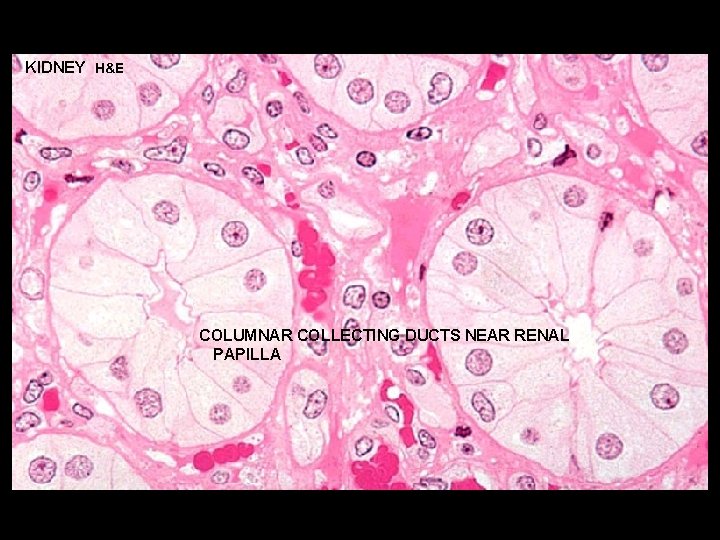

URINARY SYSTEMKIDNEY H&E CORTEX: MEDULLARY RAY 1 - STRAIGHT PORTIONS OF PROXIMAL TUBULE (THICK DESCENDING) 2 - STRAIGHT PORTIONS OF DISTAL TUBULE (THICK ASCENDING) TD C 3 - COLLECTING DUCTS - cells are cuboidal in cortex and become progressively more columnar in the medulla and papilla - cells stain very lightly with well-defined boundaries - transport urine from nephron to excretory ducts and aids in further H 2 O resorption in the presence of ADH D C D

KIDNEY H&E COLUMNAR COLLECTING DUCTS NEAR RENAL PAPILLA